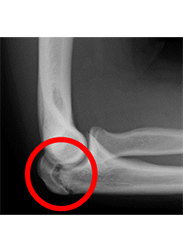

内側型野球肘の画像

肘の内側

正常

(レントゲン)

内側上顆裂離骨折